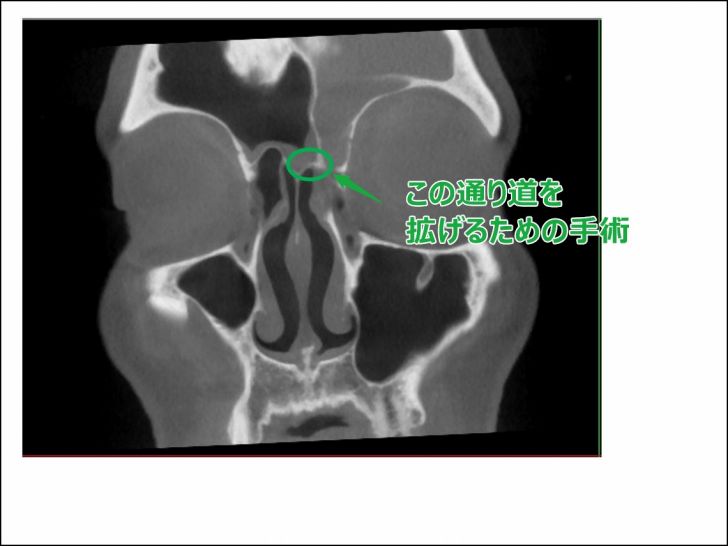

副鼻腔(前頭洞)の通り道を拡げる手術「前頭洞拡大手術」

頻繁に前頭洞炎(いわゆる前頭洞に炎症が起こる現象)を起こしてしまう場合は、手術で通り道を拡げる選択肢を取ることが多いそうです。

▼こんな手術

通り道が狭いために膿を排出出来ないということなので、その通り道を拡げてあげれば膿が溜まることを回避できるわけです。

正確な術名は分かりませんが、「前頭洞拡大手術」といったようなものです。

僕がやる手術もこれだと思ってました。ただ診断の結果そうはいかなかったんです。

なぜなら、前頭洞の広さが一般的な人の2倍あって、逆に通り道が2分の1しかないために、言わば通常よりも4倍ぐらいの負荷がかかってしまうんだとか。(結局詰まってしまうらしい)

さらに通り道のすぐ横は目になるので、拡げることが出来るのも数ミリ程度が限界だと。

数ミリ拡げただけでは、僕の2倍の空洞に溜まった膿を排出することは出来ないだろうとのことでした。